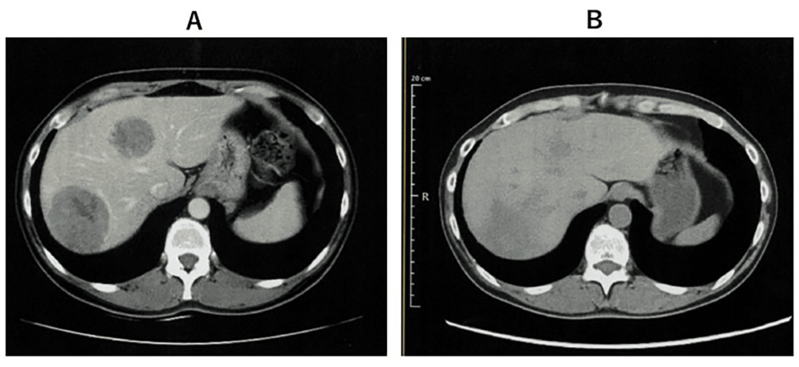

2023 年 10 月,国际期刊《Cureus》发表了一则 WT1-DC 疫苗治疗晚期肺癌的案例:69 岁男性患者确诊 “右肺中叶 IV 期鳞状细胞癌”,伴随肾上腺、肝、骨等多处转移,无法手术和放疗。医生采用 WT1-DC 疫苗联合化疗方案治疗后:

1、患者的免疫指标持续改善(淋巴细胞比例上升、炎症指标下降);

2、第 338 天胸部 CT 显示,原发和复发病灶缩小;

3、第 479 天 PET-CT 仅残留两个小转移灶,截至报道时,患者无进展生存期已超 577 天,生活正常。